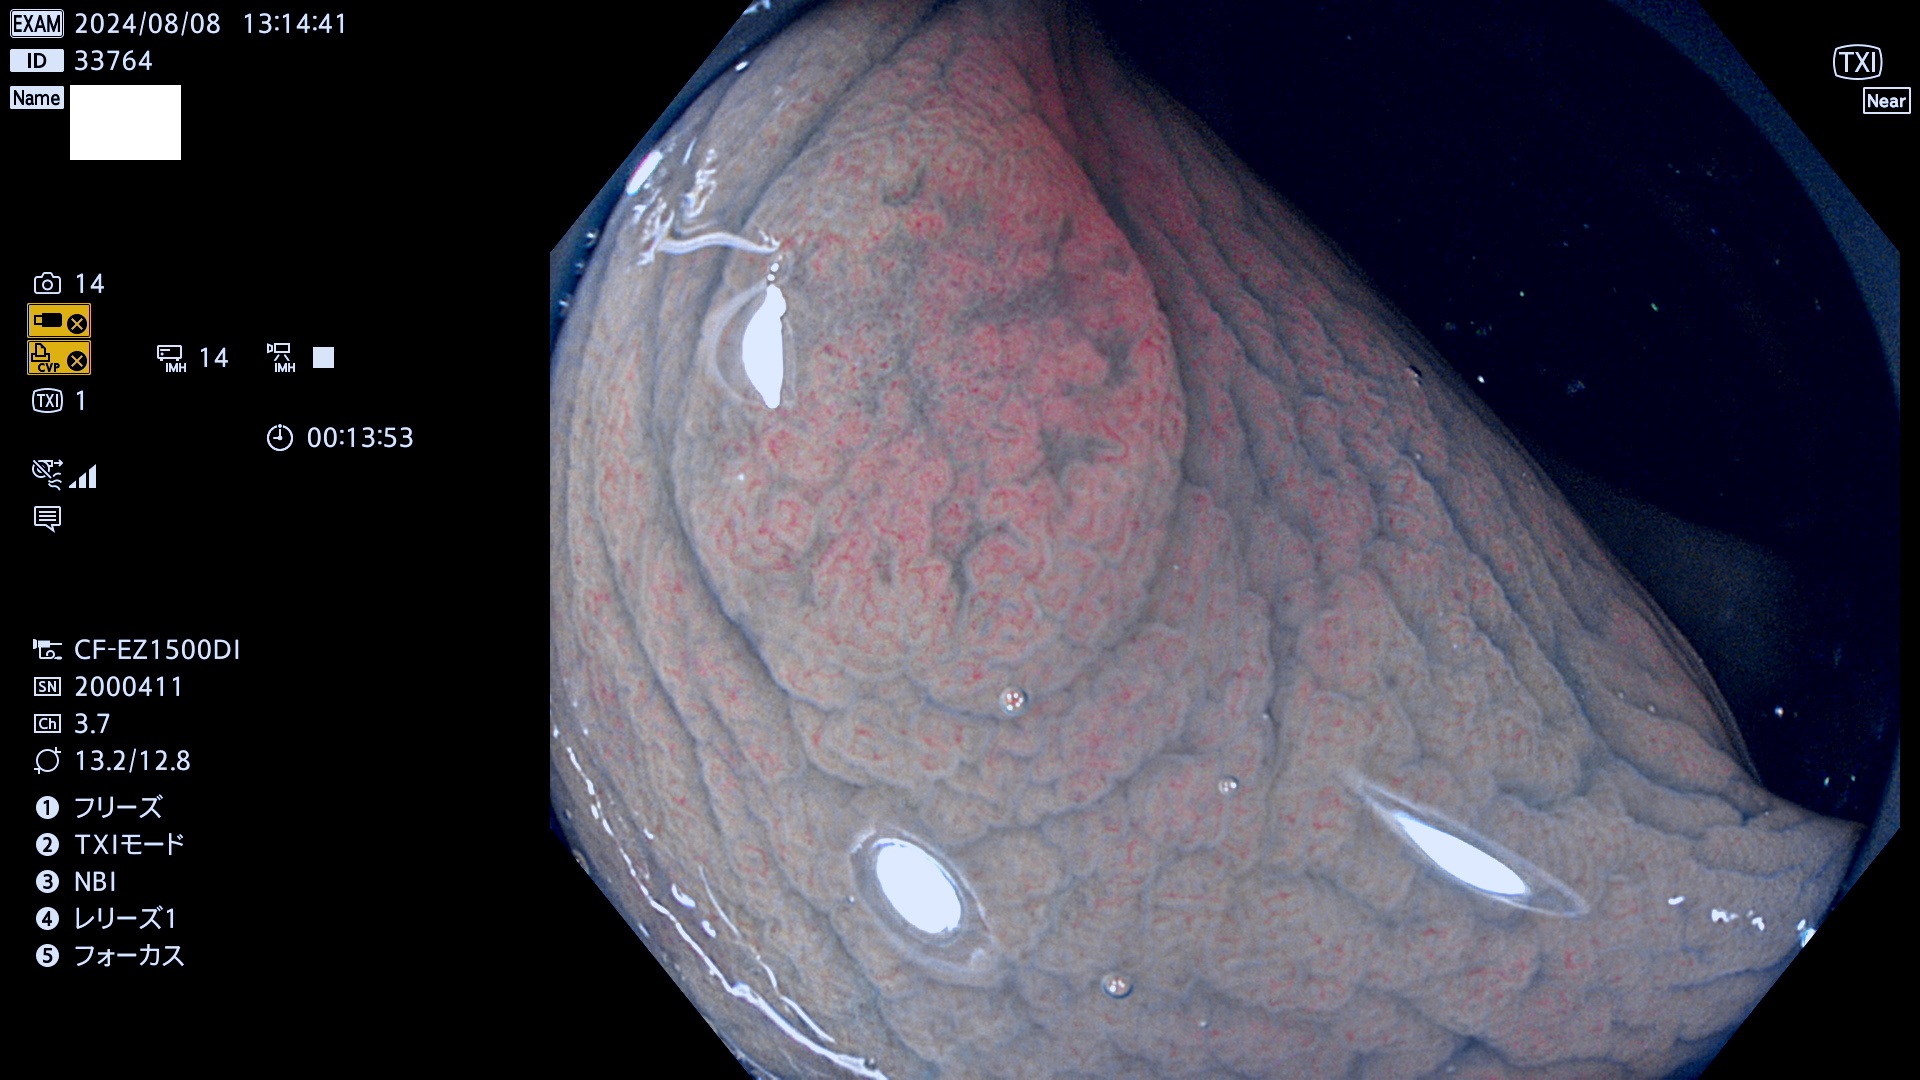

完全に平坦な物をUb、陥凹している物をUcと呼びます。最も発見が難しく危険な病変です。

抽出の対象期間 2024年8月8日〜8月11の4日間(30件の検査)11件 (11/30=35%)